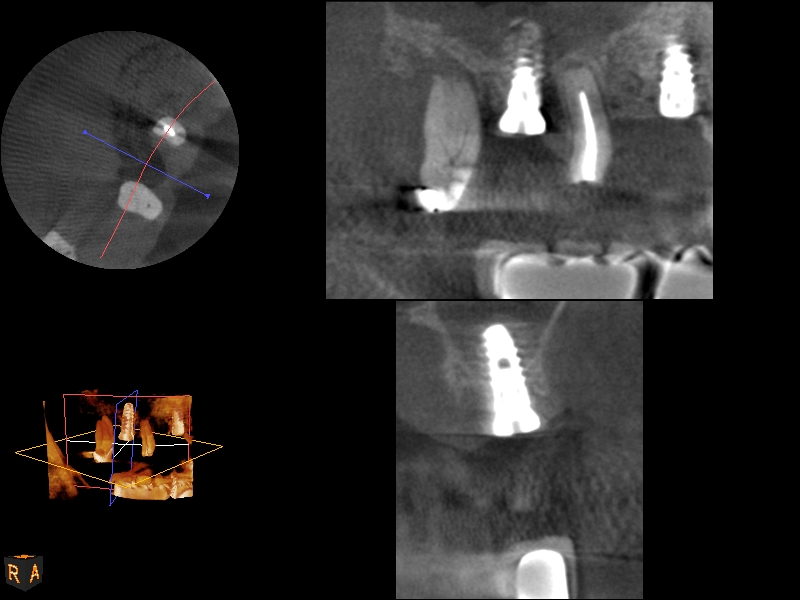

A 4-month CBCT scan (Kodak 9000D) of

implant No. 14.

Fig. 7

Because the bone grafting materials used in this technique need physical stability during healing to support the raised membrane, there is a high probability that significant shrinkage of the graft will occur as it heals and matures if only non-demineralized material is used. For these reasons, a composite graft using calcium sulfate, DFDBA, and mineralized particulate bone is used. A 50:50 mixture by volume of mineralized bone grafting material and DFDBA is used, to which approximately 40% calcium sulfate by volume is added. A higher percentage of calcium sulfate is used relative to that described for composite grafting in other uses, because some of the calcium sulfate will wash out during bone packing. Another advantage to this composite graft is that it is not as radiopaque as a purely mineralized graft. This allows radiographic monitoring of the bone healing around the implant, which can be used to time abutment placement on the implant. This is demonstrated in Figure 4 and Figure 5, which are radiographs taken on the day of the initial surgery showing the radiographic appearance of the composite graft, implant, and graft, and in Figure 6, a 5-month postoperative radiograph with the abutment in place. The old floor of the sinus is indistinguishable from the area of new bone. Figure 7 shows a CBCT scan (Carestream Dental, www.carestreamdental.com) taken at 4 months with the old floor of the sinus indistinguishable from the new bone formed.

The implant is then delivered and should be well stabilized in the bone. If there is any mobility of the implant, it can either be placed a little deeper (if there is enough native bone) or the implant can be removed and the procedure aborted, in which case it would be a two-stage procedure. This should rarely occur with the tapered designed implant, even with only 2 mm of native bone. Using a bone-level platform-shifting implant (or a tissue-level designed implant) is critical, as the hard and soft tissue will establish a biologic width. If an external hex type of implant is used and the shoulder is placed at the bone level, an expected bone loss of 1.5 mm to 2 mm will occur.24 Figure 10 shows proper bone-level implant depth placement with a platform-shifting design. In this case, a 3-mm healing abutment was placed at the time of surgery to avoid a secondary uncovering surgery, but an implant-level healing abutment could have been placed instead. As can be seen, there was only about 2 mm to 3 mm of native bone height. The membrane was raised about 8 mm to 9 mm. Comparing the radiograph on the day of surgery (Figure 10) to the 6-month postoperative radiograph (Figure 11) shows no loss of native bone, as well as the positive change in appearance of the grafted bone. The 3.5-month CBCT scan (Figure 12) shows good healing of the bone with no coronal bone loss. With minimal native bone present, as in this case, the use of a non-platform-shifting or non-tissue-level implant design could be problematic. After 1.5 mm to 2 mm of crestal bone loss, an external hex designed implant could develop instability with possible implant failure. If a non-tapered implant is used and bone loss occurs during healing, migration of the implant into the sinus could potentially occur. The surgeon can use either a healing abutment or implant-level closure screw over the implant shoulder. With patients who tend to use their tongues to explore or play with the area, or if the area is under a removable partial denture, a closure screw is recommended.